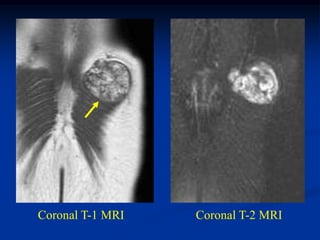

Case #1188

72 year female with

intramuscular lipoma

mid arm

Axial T-1 MRI

Case #1188 72 yearfemale with intramuscular lipoma mid arm